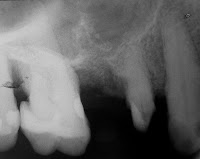

En una Rx apical se puede apreciar la estrecha vinculación del seno maxilar con la pieza en cuestión. De acuerdo a lo observado radiográficamente no es posible implantar en forma inmediata a la extracción, debido a la poca longitud encontrada en el sitio de la pieza dentaria, con motivo de la cercanía del seno maxilar.